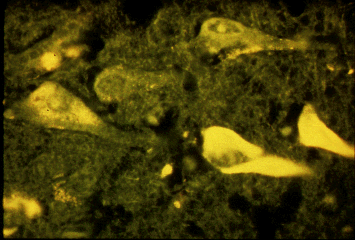

Pathology Images